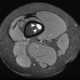

Multiple enchondromas

An enchondroma is a benign cartilage tumour found inside bones. Typically, enchondroma is discovered on an X-ray scan. [Source: Wikipedia ]